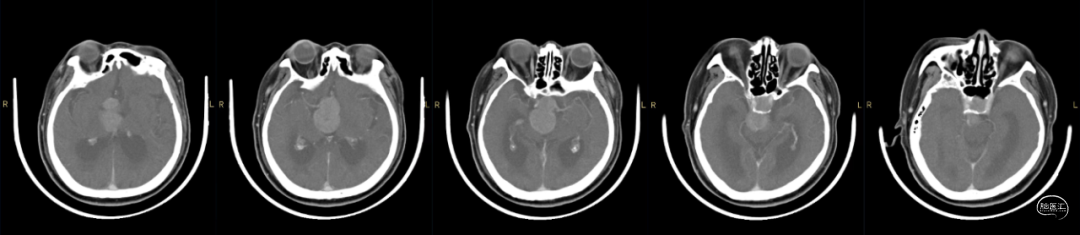

患者主诉:因双眼视物不清进行性加重5年入院。

诊断:鞍区鞍上巨大侵袭性垂体瘤。